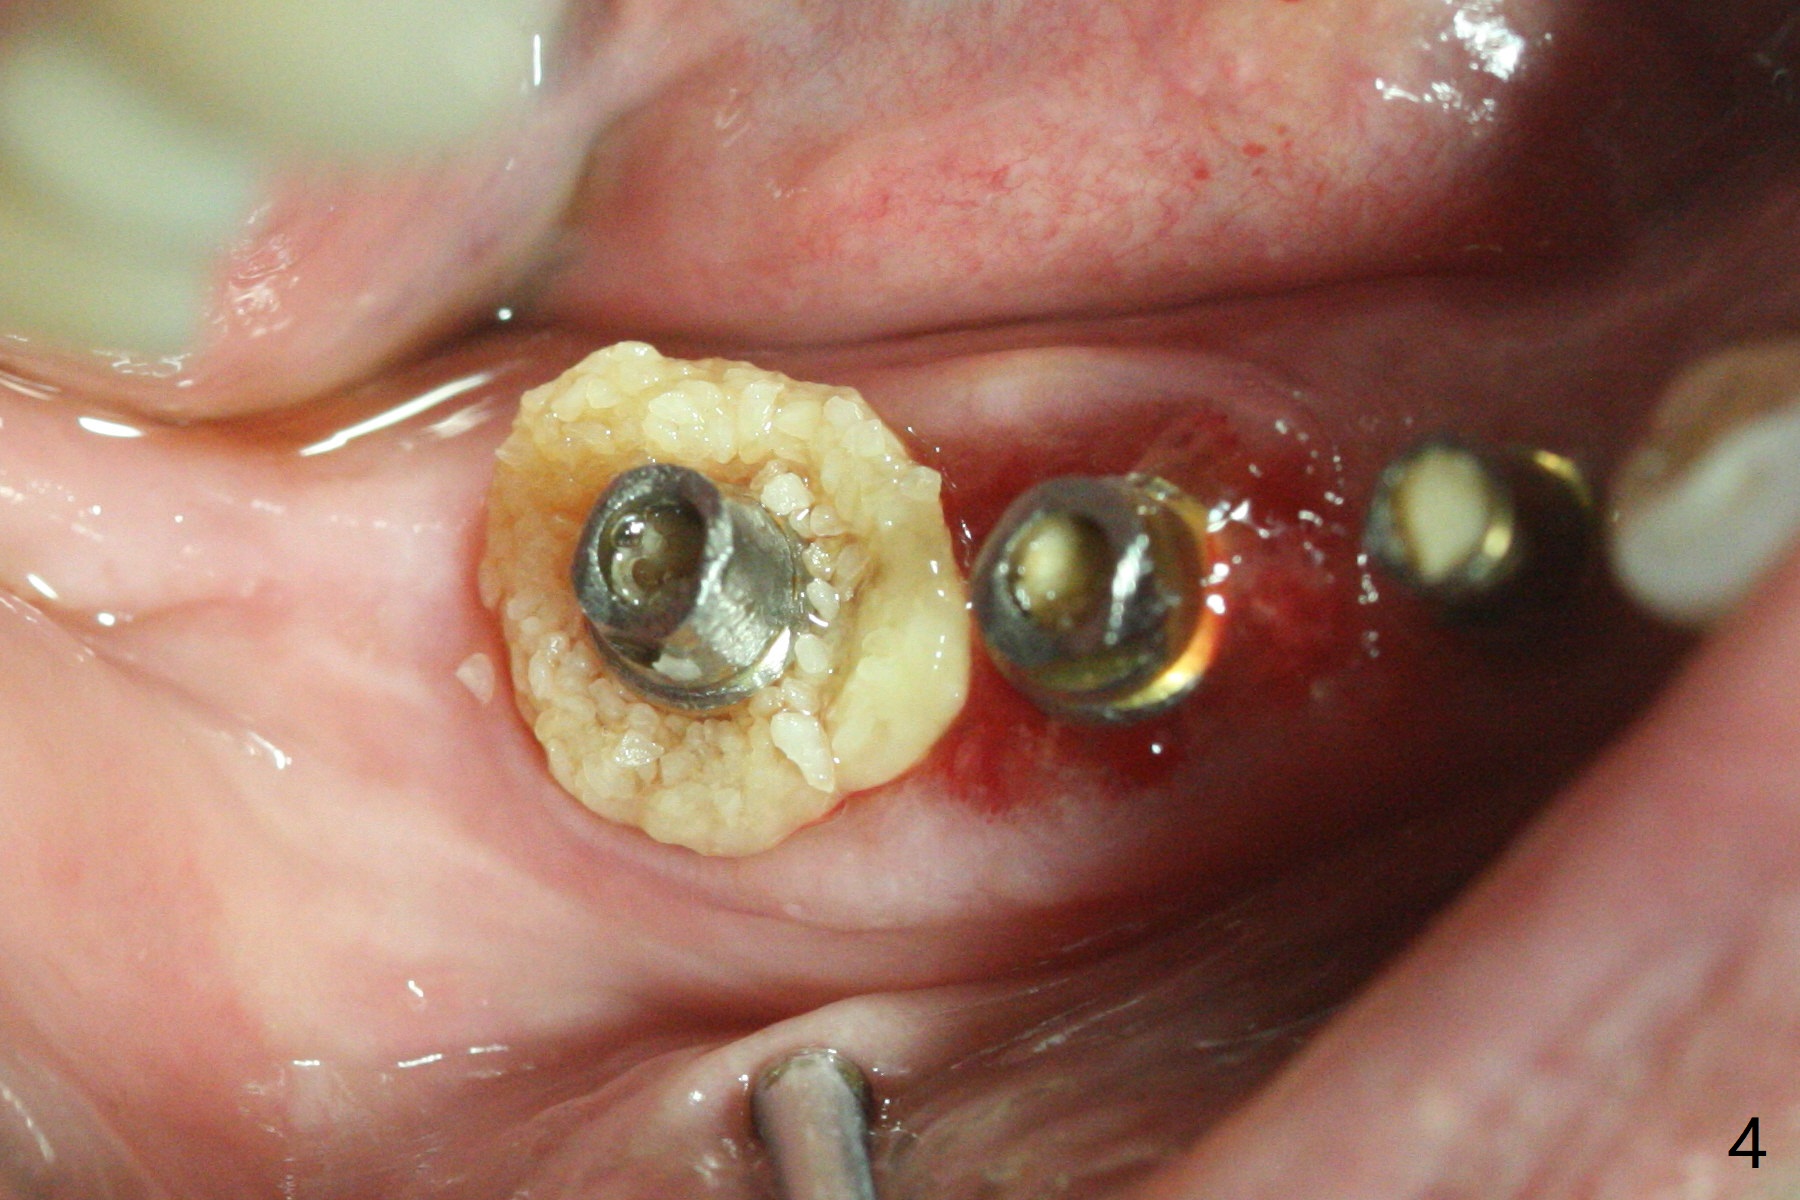

右下4-6种植后3.5月制作临时牙桥(保险的钱用完了),虽然不舒服,病人也没有及时复诊。新年过后(术后11月),她回来修复,但是临时牙桥下沉,造成牙龈退缩(图一),6螺纹暴露(图二:>),粘性骨粉中间形成一个洞眼(图三),插入6基台固定(图四),同样PRF膜也形成两三个洞眼固定在基台上(图五)。当粘性骨粉放置时,暴露螺纹已经被血凝块覆盖,舍不得去除,所以骨粉就不能接触螺纹(图六),最后用牙周敷料固定(图七),想象比树脂敷料服帖。不过2天后,牙周敷料脱落,骨粉丧失,伤口好像已经愈合(图八),没有做任何处理。今后类似病例应该在基台上涂抗病毒凡士林(以后好撤除),使用树脂敷料。Return to No Deviation Xin Wei, DDS, PhD, MS 1st edition 01/05/2021, last revision 01/08/2021